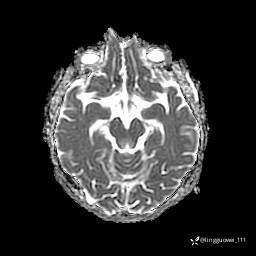

T1

img